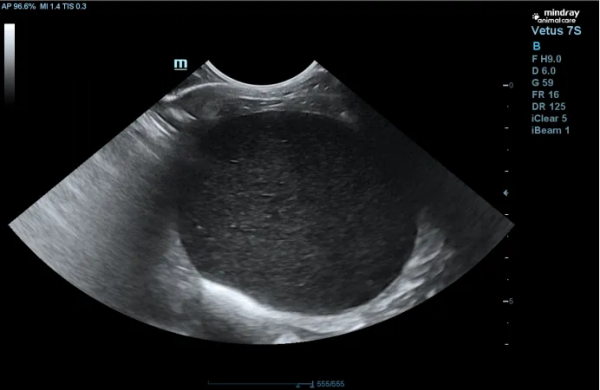

一、引言 猫痤疮是猫下颌、嘴唇部位一种常见的毛囊角质化疾病,本质是毛囊角化异常,导致粉刺(黑头)形成。轻度病例可能仅影响美观,但可继发细菌感染,发展为毛囊炎、疖病,甚至蜂窝织炎。治疗需根据严重程度分级进行,核心是局部清洁、角质溶解和控制感染。预后良好,但易复发,常需长期护理。本文报告一例9岁雄性已去势英国短毛猫因严重下颌皮肤病就诊的病例。患猫表现为严重的下颌皮肤的蜂窝织炎、食欲减退及精神沉郁。通过临床检查、细胞学及炎症指标检测,确诊为猫痤疮伴发严重的蜂窝织炎。治疗采用局部清创消毒、药用香波清洁、外用抗菌药膏,并联合系统性抗生素(阿莫西林克拉维酸钾)及情绪安抚药物进行综合管理。经过两周治疗,患猫临床症状完全缓解。本病例强调了猫痤疮继发感染时的综合诊疗思路,强调了猫痤疮的治疗总原则:局部清洁、溶解角质、控制继发感染。 二、基本信息 动物:9岁,雄性已去势,英国短毛猫,体重4.8公斤。 生活史:免疫驱虫完全,定期(每三月一次)洗澡。 主诉:近期出现频繁抓挠下巴及颈部行为,导致该部位皮肤破损出血,伴随食欲欠佳、活动量减少。 既往史:无相关病史记录。 三、检查项目及结果 挤压病变处分泌物涂片,进行染色镜检。可见大量退行性嗜中性粒细胞和巨噬细胞 皮肤刮片检查:未见寄生虫 血检:WBC:28.7; Neu:13.06;SAA:67.83; 结果:B超扫查发现,膀胱充盈,膀胱壁欠光滑,腔内充满产回声内容物,提示膀胱内有泥沙样结晶。 四、诊断结果 病史与临床检查:根据特征性的发病部位(下颌)和临床症状(粉刺、丘疹等),通常可做出初步诊断为猫痤疮。病因待进一步确认。 五、治疗方案及预后 剪短患处毛发,注意不是剃毛以防进一步的毛囊应力损伤,给患处消毒,每周1-2次用泡泡爽宠物清洗剂清洁,每日涂抹抑菌膏,口服阿莫西林克拉维酸钾干混悬剂(克维舒),每次1ml,一日两次;配戴脖圈,防止抓挠,每日两次宠物情绪调节营养补充剂(舒欣宝)每次1条缓解瘙痒情绪,治疗2周病变处症状显著改善。继续使用一周抗生素。 清洁后的照片 治疗第一周的照片 治疗第二周,痊愈照片 六、讨论及小结 猫痤疮为猫常见的一种皮肤病,为下颌组织及腺体的囊泡性角化及腺体增生,此病例为中重度的猫痤疮,继发细菌感染,引起毛囊炎、疖病。表现为疼痛性肿胀、囊肿、瘘管,按压有脓血排出。除了局部清洁用药外,同时使用抗生素治疗控制继发感染,并使用情绪舒缓产品辅助治疗,本次治疗我们选用了更适宜猫咪的口服抗生素与情绪舒缓产品。首要考量是避免因强制喂药牵扯下颌,引发额外疼痛;同时,我们也希望借助更易喂服的口服片剂,来降低宝贝的紧张感,从治疗本身提升它的就医体验。 阿莫西林和克拉维酸钾(克维舒)适应证:犬用于治疗犬由产β-内酰胺酶的金黄色葡萄球菌,不产β-内酰胺酶的金黄色葡萄球菌,葡萄球菌属,链球菌属和大肠杆菌引起的皮肤和软组织感染,如创伤、脓肿、蜂窝织炎、浅表性/幼年性和深层脓皮病;由需氧和厌氧敏感菌引起的牙周感染。猫:用于治疗猫由产β-内酰胺酶的金黄色葡萄球菌,不产β-内酰胺酶的金黄色葡萄球菌,葡萄球菌属,链球菌属,大肠杆菌,多杀性巴氏杆菌和巴氏杆菌属引起的皮肤和软组织感染,如创伤、脓肿、蜂窝织炎。 进一步探讨关于猫痤疮难治性或慢性病例的考虑 对于常规治疗无效的病例,可考虑以下方案: 维生素A:口服维生素A或外用维A酸软膏(Retin-A)。注意:维A酸对猫刺激性大,需非常谨慎使用,且价格昂贵。 全身性糖皮质激素:如果瘙痒和炎症非常严重,可短期口服泼尼松龙片(1-2 mg/kg,每日一次,症状控制后迅速减量),以打破瘙痒-感染的恶性循环。但需谨慎使用。 排查潜在病因:如果痤疮反复发作或治疗效果不佳,应深入排查是否存在食物过敏、过敏性皮炎等潜在问题。 预后:通常预后良好。但猫痤疮是一种慢性、易复发的疾病,很多病例需要终生间歇性的对症治疗和护理。 给主人的建议: 1. 坚持日常护理:症状缓解后,仍需定期使用药用香波清洗下颌(如每周1次),作为预防。 2. 使用陶瓷或不锈钢食盆:避免使用塑料食盆,因其表面易刮擦藏匿细菌。 3. 保持清洁:饭后擦拭猫的下颌,保持该区域干燥清洁。 4. 避免刺激:切勿用手挤压粉刺,这会加重炎症和感染。 5. 遵从医嘱:如果医生开了抗生素,务必完成整个疗程,不可自行停药。 七、参考文献 《猫病学》 第5版 《小动物皮肤病学》 第7版